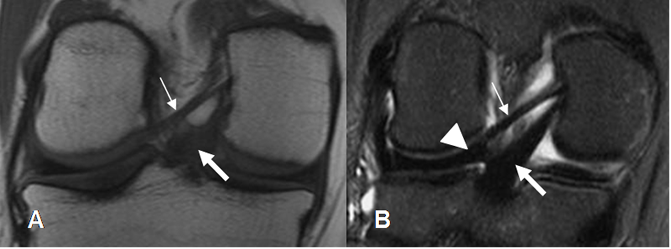

Fig 19. Ligamentos meniscofemorales normales.

A: RM coronal en T1 y B: RM coronal en STIR. Ligamento menisco femoral posterior (Flecha delgada), en relación con el LCP (Flecha gruesa). Menisco externo (Punta de flecha).